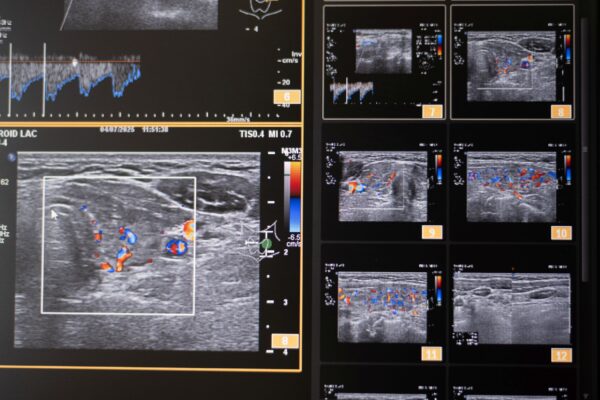

Color Doppler je temeljen na ultrazvučnoj tehnologiji koja pomoću Doppler-ovog efekta procjenjuje prokrvljenost cijele štitnjače i čvorova u štitnjači, kao i limfnih čvorova vrata. Pomoću color Dopplera računamo brzine protoka kroz krvne žile koje hrane štitnjaču, čime dobivamo važne hemodinamske parametre. Na temelju ovih pokazatelja donosimo važne dijagnostičke zaključke, te efikasno pratimo efekte liječenja štitnjače.

Ultrazvuk štitnjače i vraza sa color dopplerom